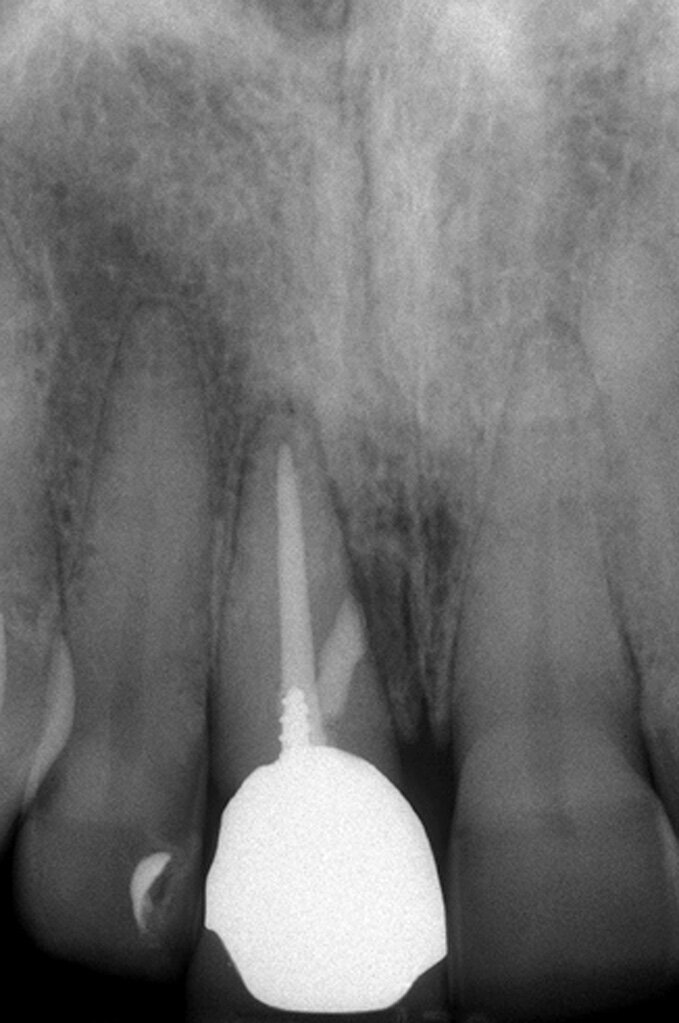

Riparazione delle perforazioni mediante l’uso di MTA

La prognosi delle perforazioni è enormemente migliorata dopo l’introduzione dell’utilizzo del microscopio operatorio14 e del materiale biocompatibile MTA15, messo a punto da Torabinejad e coll.16 circa a metà degli anni ’90. Si tratta di un cemento endodontico estremamente biocompatibile, idrofilo e capace di stimolare processi di guarigione e osteogenesi17, 18. È una polvere di fini triossidi e altre particelle idrofile che induriscono in presenza di umidità. L’idratazione della polvere, infatti, dà luogo ad un gel colloidale che solidifica in una struttura dura in circa 3/4 ore. Tale cemento è diverso da tutti gli altri materiali usati per la sua biocompatibilità, per la sua attività antibatterica, per il suo adattamento marginale, per le sue capacità sigillanti ma soprattutto perché è idrofilo e quindi è resistente all’umidità.

Come già accennato prima, la caratteristica che contraddistingue l’MTA da tutti gli altri materiali usati per riparare le perforazioni iatrogene è rappresentata dal fatto che è idrofilo. I materiali usati per riparare le perforazioni, per sigillare la cavità retrograda in endodonzia chirurgica, per otturare gli apici immaturi o per proteggere il tessuto pulpare negli incappucciamenti pulpari diretti, sono tutti inevitabilmente in contatto col sangue o con altri fluidi tissutali. L’MTA è l’unico materiale che non è influenzato dall’umidità né dalla contaminazione da parte del sangue19. D’altra parte, l’MTA indurisce solamente a contatto con l’umido. Pertanto, per le suddette caratteristiche e soprattutto per la sua idrofilia, l’MTA può oggi essere considerato il materiale di elezione per sigillare le perforazioni iatrogene o patologiche20-23.